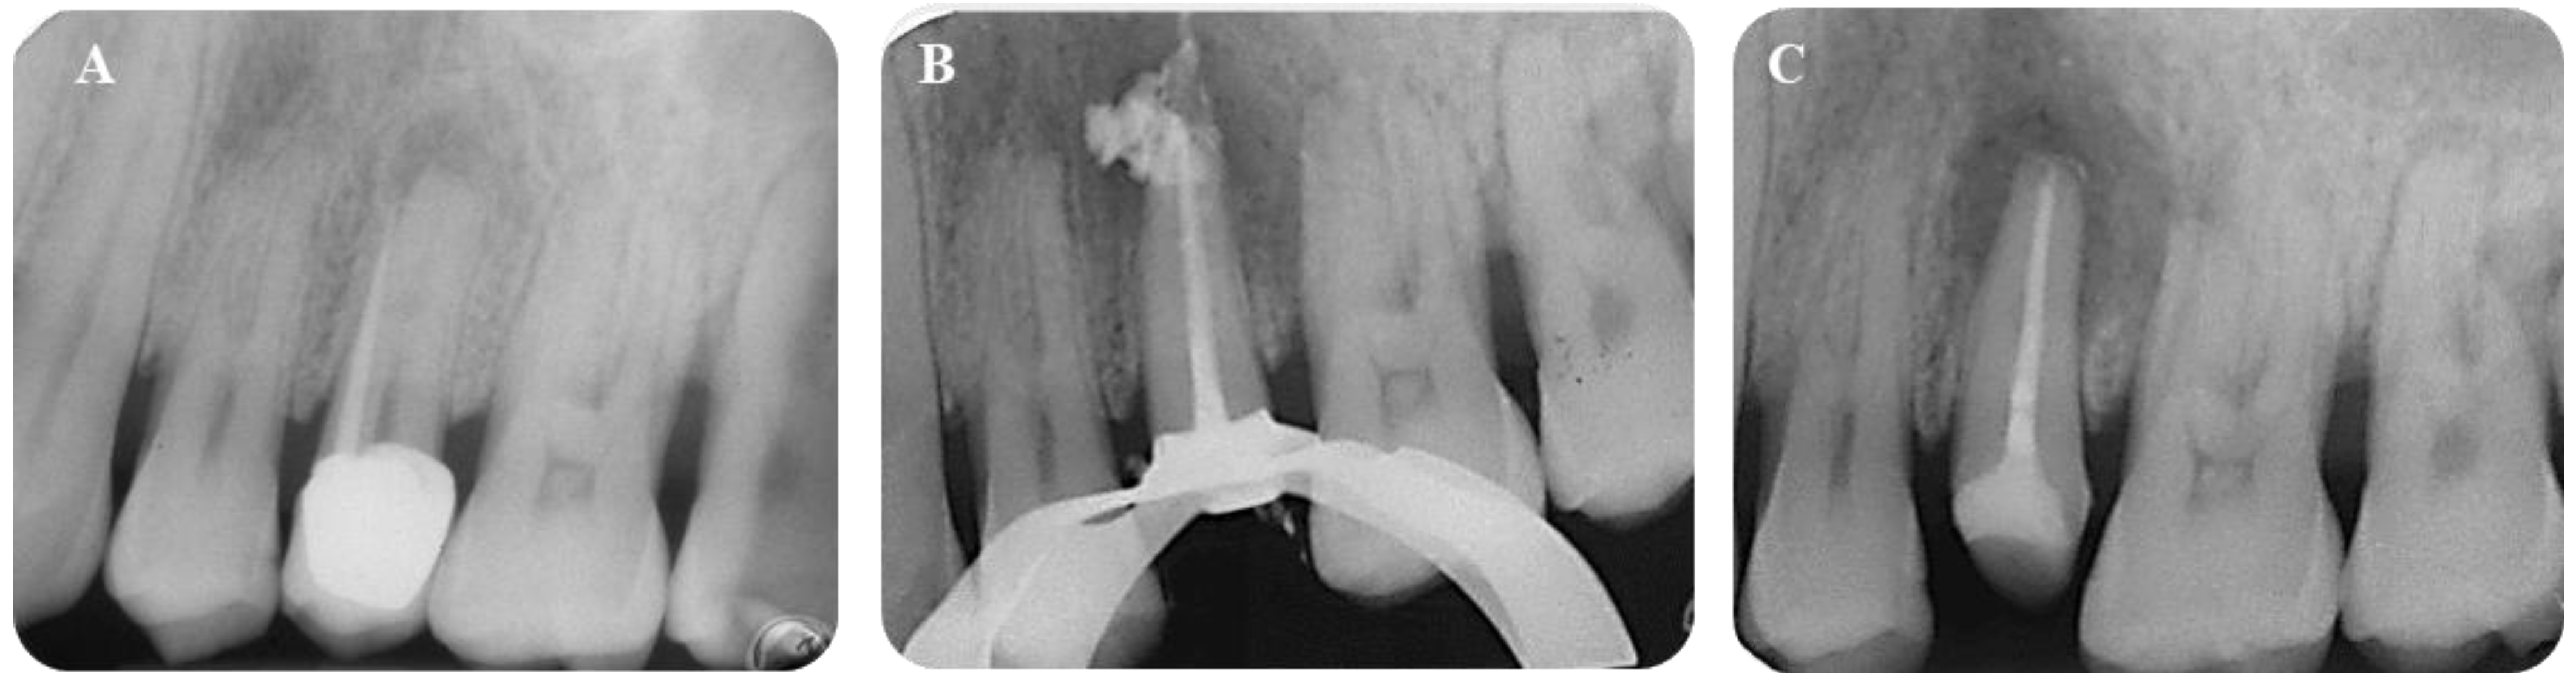

Bioceramic Sealer Technique . I also changed to this sealer because. This chapter highlights the usage of the newer generation bioceramic sealer in three different cases of nonsurgical root canal. The main functions of root canal sealers are (i) sealing off of voids, patent accessory canals, and multiple foramina, (ii).

This chapter highlights the usage of the newer generation bioceramic sealer in three different cases of nonsurgical root canal. The main functions of root canal sealers are (i) sealing off of voids, patent accessory canals, and multiple foramina, (ii). I also changed to this sealer because.